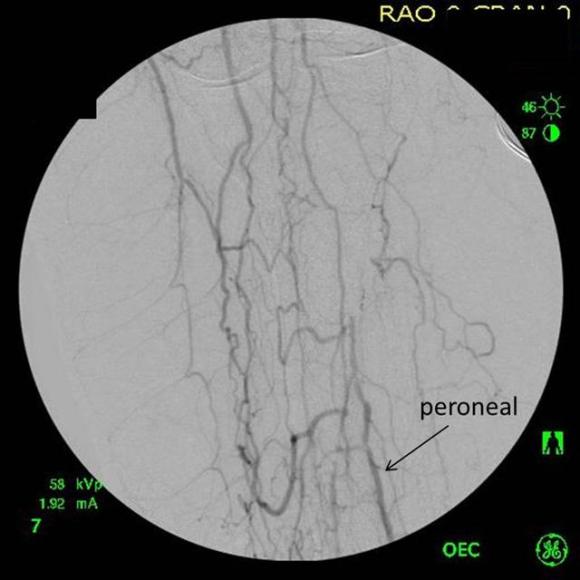

Examination revealed a fit and trim man in his 70’s in no apparent distress. He had bilateral leg edema that was moderate with small superficial and tender ulcers of the right posterior distal calf. Pulses were normal. He was taken to our hybrid suite and venography from femoral vein access in the proximal thigh in the supine position revealed his right and left iliac venous systems to be occluded (below figures).

Wire access into the iliac systems was performed with Glidewire and Glidecatheter periodic venography to confirm that I had not exited the vein. Unlike the arterial system, extravasation from being extravenous does not have the consequence of bleeding, hematoma development, and pseudoaneurysm formation because of the low pressure, but it can be a long procedure and uncomfortable as well so these are done under general anesthesia.

Once position confirmed to be in the iliac vein, the vein was dilated to allow for greater ease of movement. In the case of the uncrossable filter, I switched to access from above via a right internal jugular vein access.

Once the wire crossed into the iliac vein from above, it was captured and brought out. While ballooning by itself is inadequate for revascularization, it greatly eases wire capture and on the right, it was done simply by driving the wire from above into the sheath. Wire capture wins access across the iliocaval and IVC filter occlusion from below.